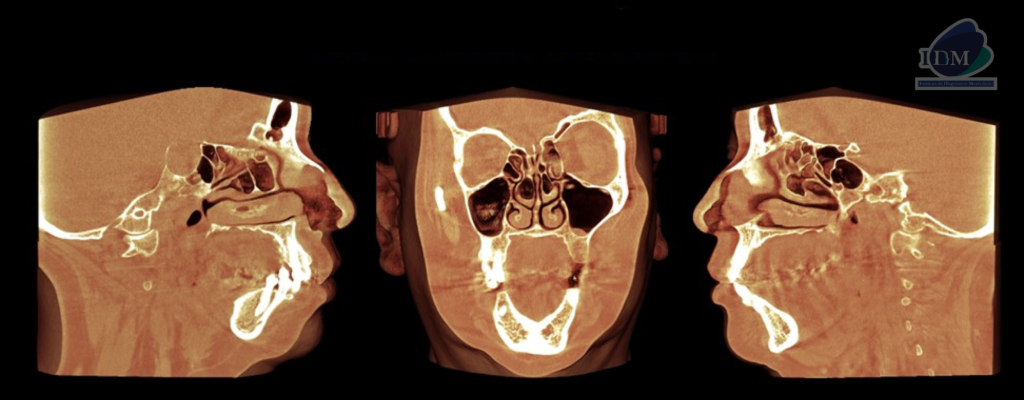

CORTES SAGITALES

RECONSTRUCCIÓN 3D